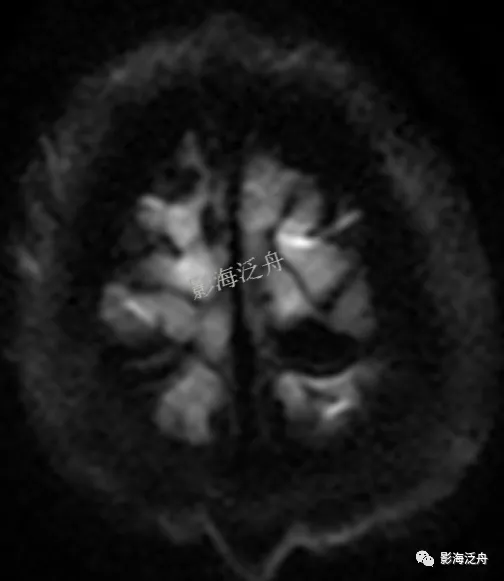

这个病例最大的疑点就在于上面两幅图,分别是高b值DWI和低b值DWI序列。为了搞明白DWI信号丢失的原因,我特意请教了philips的蒋强盛老师,在此对蒋老师表示感谢!

• DWI序列采用EPI方式采集信号,由于只有一个回波链,因此被激发的质子群只要在被激发后的第一时间受到细微运动的干扰(如缓慢的静脉血流),其横向磁化矢量就会很快衰减,同时导致后面的信号全部缺失;

• 病灶位于颅顶部,处于颅骨-血管-脑脊液/脑组织交界面区,不同组织间质子量差异很大而距离又比较近,就容易形成磁敏感伪影;

• 静脉血流本身具有磁敏感差异;

• 血液流动(但并非流空)。

为了加深印象,我找到了不同类型脑膜瘤的DWI表现:以周围脑实质作为参照,脑膜瘤在DWI上可以是高信号~等信号~低信号,这与病灶内部组织细胞的密集程度以及是否出血等因素相关。不难发现,除了出血,脑膜瘤在DWI上一般不会出现信号丢失;但即便有出血,信号也比较混杂,不会像本病例一样出现均匀一致的信号丢失。